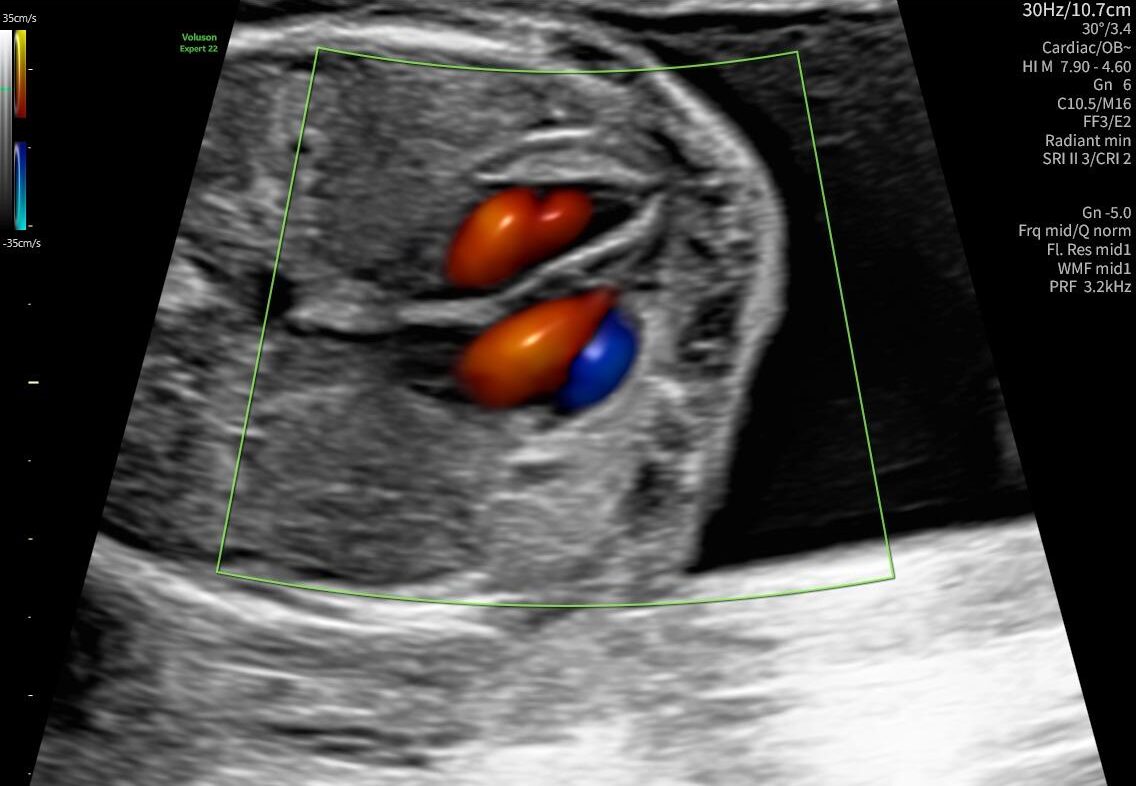

La ecocardiografía fetal es un estudio ecográfico avanzado que permite analizar con detalle la estructura y el funcionamiento del corazón del bebé antes de nacer. Este examen ayuda a identificar posibles alteraciones cardíacas y a evaluar el desarrollo adecuado del sistema cardiovascular fetal.

A través de imágenes ecográficas de alta precisión, los especialistas pueden observar las cavidades del corazón, las válvulas y el flujo sanguíneo, lo que permite realizar un diagnóstico prenatal más completo.